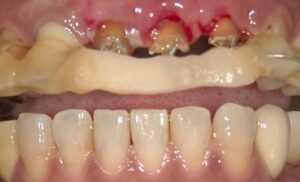

歯が提出され、その場合歯茎ごと上がってきますので

歯茎を切除します。その後の画像です。

土台(コア)を装着したところです。